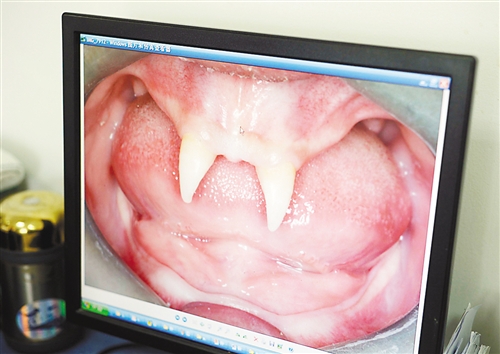

12月18日,16歲的張成(化名)從小到大,只有上顎部分有兩顆牙,看上去更像長(zhǎng)著一對(duì)獠牙。 記者熊明攝

重慶日?qǐng)?bào)訊 每個(gè)人都有牙齒,但對(duì)16歲的張成(化名)來說,從小到大,他只有上顎部分有兩顆牙,看上去更像長(zhǎng)著一對(duì)獠牙,這讓他很自卑又易怒。12月18日,在母親的陪同下,他來到三軍醫(yī)大西南醫(yī)院求助。經(jīng)醫(yī)生檢查,發(fā)現(xiàn)張成患有一種罕見的基因病。

張成是貴州銅仁地區(qū)思南縣人,從生下來就似乎得了一種怪病,身上毛發(fā)稀少,面部發(fā)育也不好。更奇怪的是,別人家的孩子都長(zhǎng)牙吃東西了,他卻一直長(zhǎng)不出牙齒,最后只在上顎部分冒出兩顆比較突出且對(duì)稱的牙齒,看起來就像一對(duì)獠牙。

在母親陪同下,張成來到西南醫(yī)院口腔頜面外科就診。經(jīng)醫(yī)生檢查,張成被確診為無汗型外胚層發(fā)育不良。

據(jù)介紹,該病的發(fā)病率不到十萬分之一,是一種較為罕見和嚴(yán)重的基因病,多見于男性。如果患上這種病,其乳牙或恒牙會(huì)先天性缺失,還可能伴隨淚腺發(fā)育障礙、視光敏感、視力下降、聽力障礙、唇腭裂、發(fā)音困難、身材矮小、乳房發(fā)育不良等癥狀。以西南醫(yī)院為例,每年都會(huì)遇見一兩例這樣的患者,但像張成這樣嚴(yán)重的,非常少見。